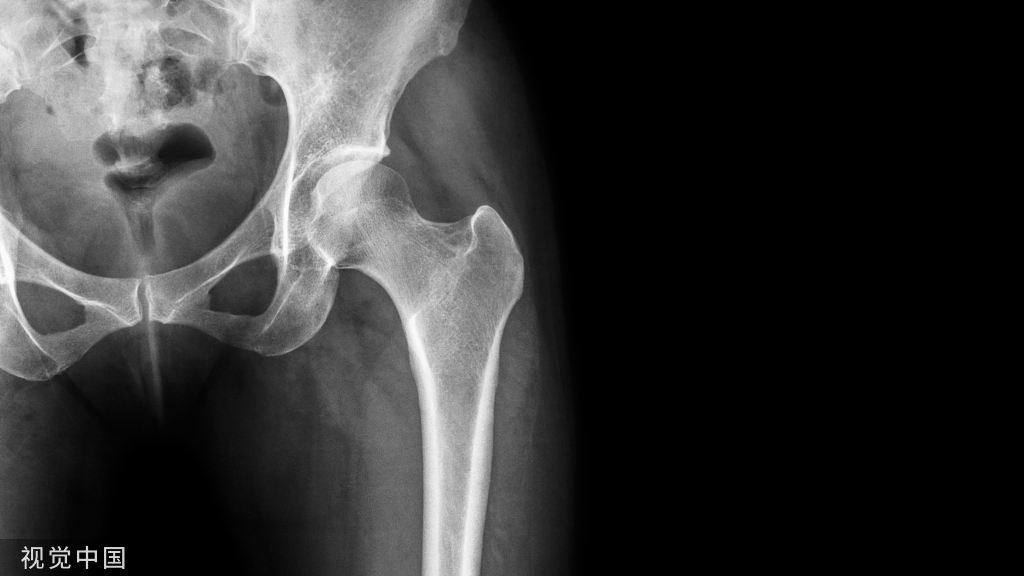

全身各部位的肌肉、韧带.筋膜、腱鞘、滑膜的急慢性损伤或退行性变,都适合应用封闭疗法,骨关节病亦适用。